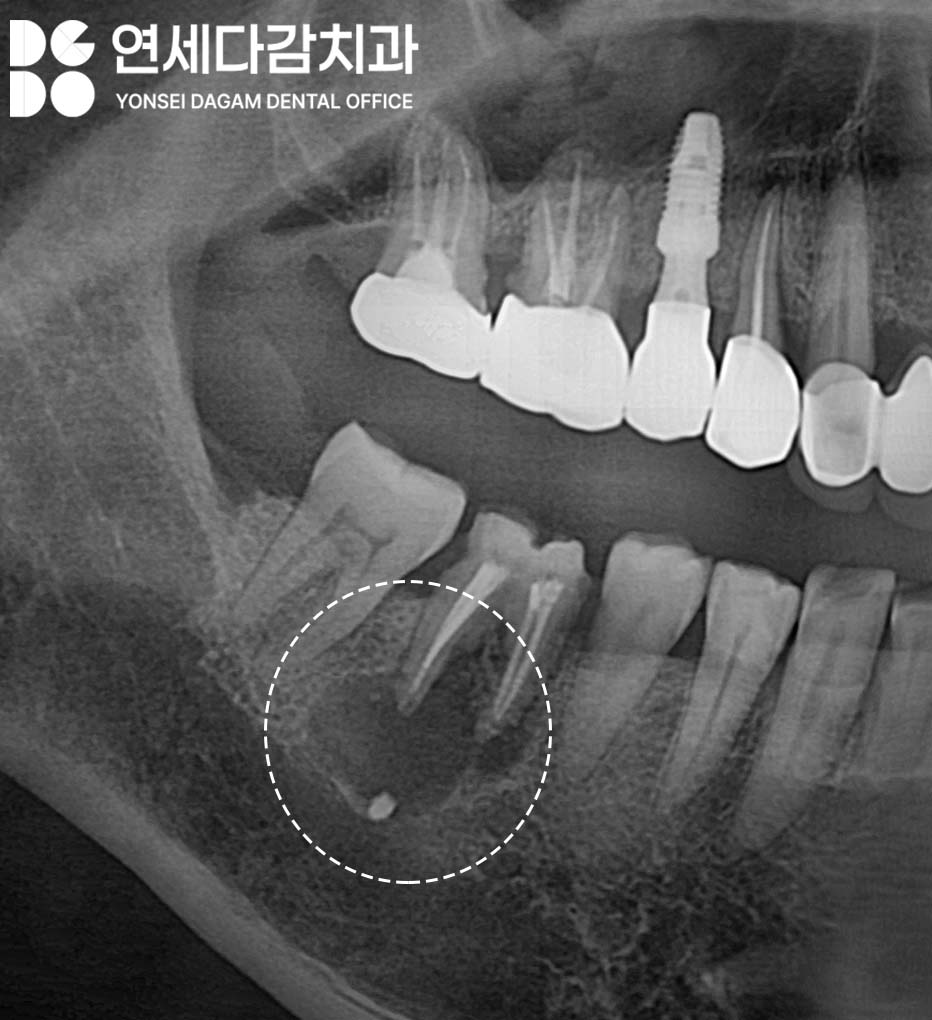

엑스레이 촬영을 하면 투과성으로

치아 뿌리 끝에 검은 그림자처럼

나타나는 것이 특징입니다.

개롱역 치과 에서 서문에서 언급한

원인들 외에도

과거에 근관치료를 받았던 곳이

재감염이 되면

치근단 병소가 생길 수 있습니다.

특히 기존에 크라운을 씌운 치아의

보철물이 빠졌을 때

탈락된 채로 방치하면,

음식물이 쉽게 잔류하게 되고

균에 직접적으로 쉽게 감염될 수 있는

환경이 됩니다.

그러나 이미 근관치료가 되어있고

낭종의 크기가 커서

뼈를 광범위하게 파괴하고 있다면

수술적 접근이 필요합니다.